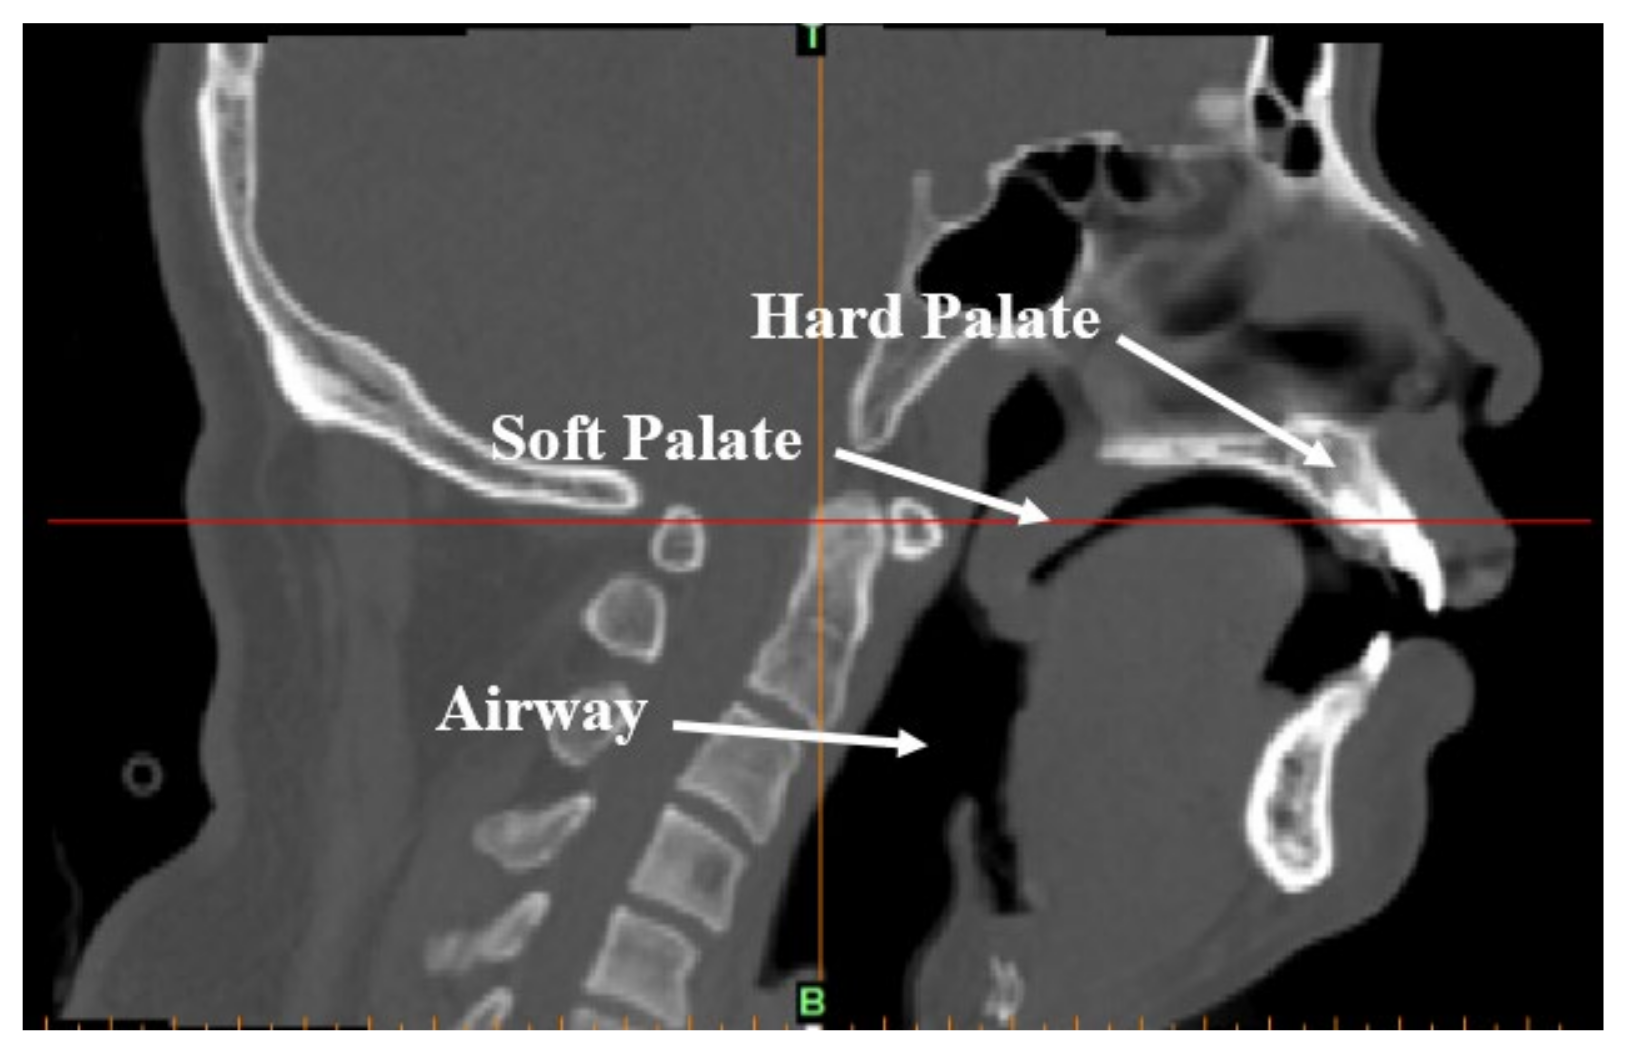

For minimizing the time in putting the patient to natural sleep for the scan, and eliminate the effect of tranquilizing drugs, the patient was required to stay awake for the entire night prior to the experiment and avoid consuming beverages or taking medication that was naturally exciting or tranquilizing before the examination. The patient was expected to sleep naturally in a supine position before the CT scan could commence. When the patient began to snore, the medical staff called the patient’s name gently and the patient did not wake up, confirming the patient was in a state of deep sleep. A Dy-volume scan from the basis cranii to the cricoid cartilage was performed on the patient using a Toshiba Aquilion ONE 640-slice dynamic organ volume CT scanner (Toshiba, Tokyo, Japan) to obtain the CT data of the patient’s upper airway during natural sleep, as shown in Figure 1. The scan time was set to 10 s and the scan thickness was 0.5 mm. When the scan was completed, DICOM format images were obtained and are shown in Figure 2.

Figure 2.

CT-scanned image of the upper airway of an OSAHS patient in a supine position and sleeping naturally.